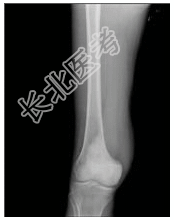

- [材料题] 患者男,21岁,右股骨下端肿痛2月余。查体:右股骨下端压痛,肿胀,可触及软组织肿块。行股骨下段正侧位片检查。

- 简答题1、患者的诊断及依据是什么?

- 简答题2、鉴别诊断是什么?